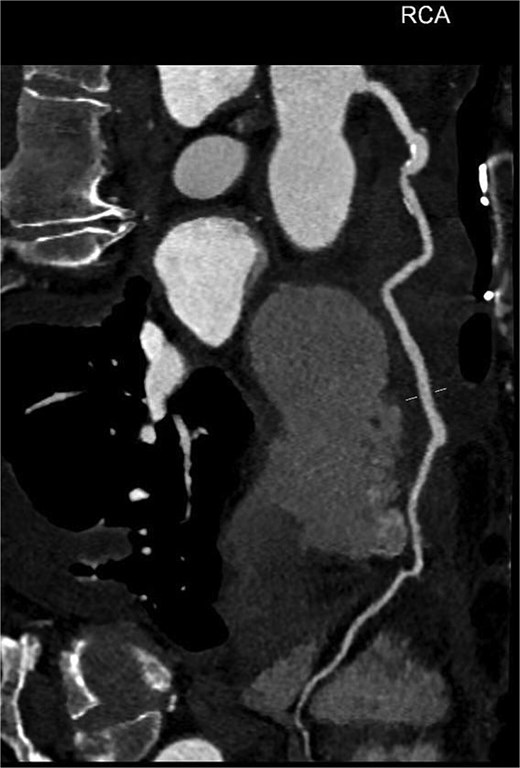

An 82-year-old female presented to the emergency department complaining of progressive severe central chest that was pleuritic in nature, radiating to her right arm. Following a bedside echo, the patient underwent coronary angiography, where a giant right CAA was diagnosed (Fig. 1). Subsequent, contrast computed tomography (CT) scan further characterized the aneurysm, and highlighted significant compression was uncovered compressing both the right atrium and ventricle (Fig. 2). The right coronary aneurysm was measured cross-sectional dimensions of 8.3 × 7.4 cm (Fig. 3) and 10 cm in length (Fig. 4). Following Heart Team discussion, the patient was scheduled for an aneurysmectomy and coronary artery bypass to repair the extensive disease.

Coronal plane of a contrast thorax CT scan showing the giant coronary aneurysm.